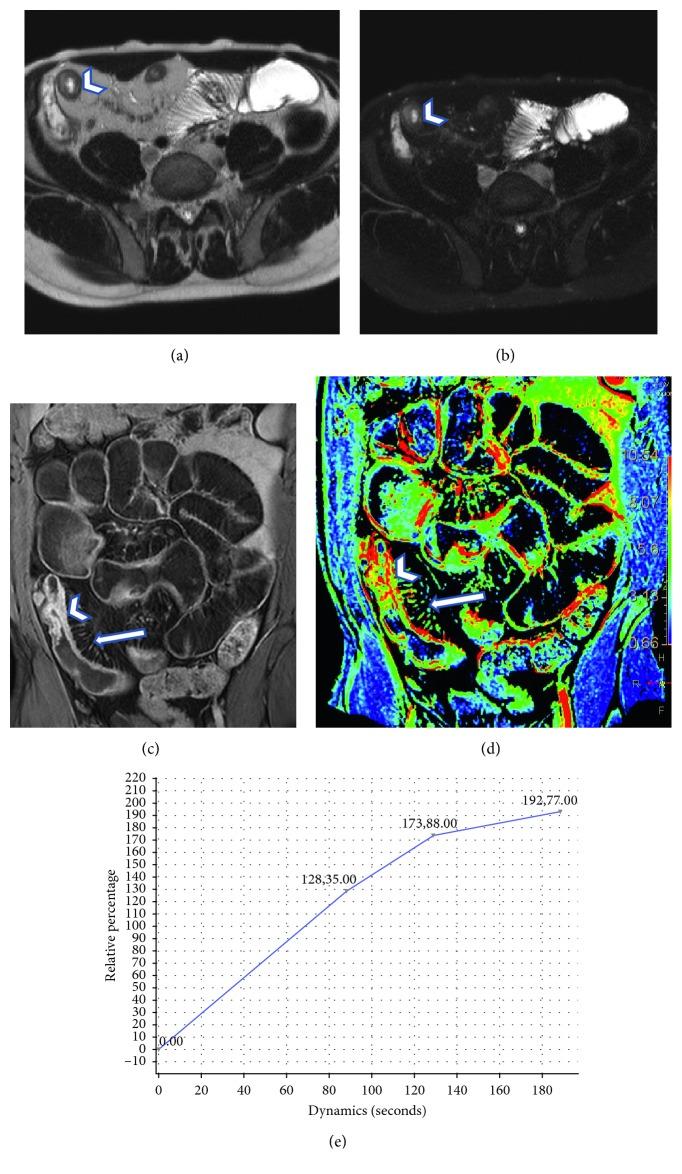

We analyzed a total of 37 (11 women; 23-69 years) patients with known biopsy proven CD, who underwent MR-enterography (MRE) study, performed on a 1.5 T MRI system (Achieva, Philips), using a phased array sense body multicoil, after oral administration of 1.5-2 L of PEG solution. MRE protocol included T1 weighted, SSh T2, sBTFE, and gadolinium-enhanced THRIVE sequences acquired on coronal and axial planes. A dedicated workstation was used to generate perfusion color maps, on which we drown ROI on normal bowel and on pathological segment, thus obtaining related perfusion parameters: relative arterial, venous, and late enhancement (RAE, RVE, and RLE), maximum enhancement (ME), and time to peak (TTP).

RESULTS

Quantitative perfusion analysis showed a good correlation with local degree of Crohn's inflammation activity. Twenty-nine out of 37 patients showed active inflammatory disease (reference standard of active disease: wall bowel thickness and layered enhancement) with following perfusion parameters: REA (%) = 116.1, RVE (%) = 125.3, RLE (%) = 127.1, ME (%) = 1054.7, TTP (sec) = 157. The same parameters calculated in patients with mural fibrosis were as follows: RAE (%): median = 56.4; RVE (%): 81.2; RLE (%): 85.4; ME (%):809.6; TTP (sec): 203.4. A significant difference ( < 0.001) between inflamed and fibrotic bowel wall vascularity, regarding all perfusion parameters evaluated, was found, with higher values in active CD localizations.

我们分析了 37 例(11 名女性;23-69 岁)经活检证实为 CD 的患者,这些患者均在 1.5T MRI 系统(Achieva,Philips)上进行了磁共振肠道成像(MRE)检查,使用了相控阵体多线圈,在口服 1.5-2L 的 PEG 溶液后进行。MRE 方案包括冠状位和轴位的 T1 加权、SSH T2、sBTFE 和钆增强 THRIVE 序列。使用专用工作站生成灌注彩色图,在正常肠段和病理节段上画出 ROI,从而获得相关灌注参数:相对动脉、静脉和晚期增强(RAE、RVE 和 RLE)、最大增强(ME)和达峰时间(TTP)。

结果

定量灌注分析与局部 CD 炎症活动程度具有良好的相关性。37 例患者中有 29 例(参考标准为活动性疾病:肠壁厚度和分层强化)显示出活动性炎症性疾病,其灌注参数如下:REA(%)=116.1、RVE(%)=125.3、RLE(%)=127.1、ME(%)=1054.7、TTP(sec)=157。在壁纤维化患者中计算出的相同参数如下:RAE(%):中位数=56.4;RVE(%):81.2;RLE(%):85.4;ME(%):809.6;TTP(sec):203.4。在所有评估的灌注参数方面,活动性和纤维化肠壁血管性之间存在显著差异(<0.001),活动性 CD 病变部位的灌注参数更高。